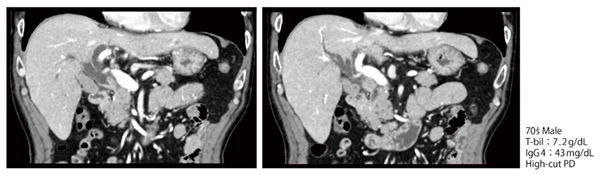

●症例3:遠位胆道がん(70歳代、男性)

本症例は結節型腫瘍があり、上流側の拡張が見られた(図5)。膵頭十二指腸切除術は必要であると考えられ、上流側の進展範囲診断目的にERCPを施行した。

通常、左右の胆管は約30°〜40°傾いているため、Cアームを回転させることで正面視できる(図6 a)。一方、背骨に対して正面視した場合は、左右の合流部と背骨の間には距離があるが(図6 b)、Cアームを斜めに傾けると距離が短くなる(c)。特にCアームを回転させ、左右胆管の分岐を明瞭に描出しようとすると、左胆管は背骨と重なる部分が多くなる。そのため、Cアームの角度は症例に応じて判断する必要がある。

また、本症例のMR胆管膵管撮影(MRCP)の画像を用いて、ERCPにおけるCアームの角度について検討した。B4を正面視する角度ではB2+3と重なるが(図7 b)、斜めから見る角度にMRCP画像を回転させるとB4が分離して見えることがわかる(c)。この結果により、Cアームを足側に回転させたことでB4合流部の形態が明確に描出されたことが理解できる(図8)。